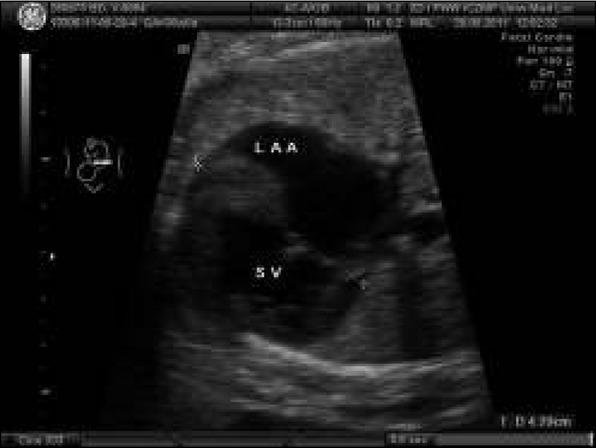

Abnormal fetal heart (fetus in cephalic presentation, longitudinal position I): common atrium with left atrial appendage (LAA) on the right side of the fetal heart, single atrioventricular valve opening to single ventricle with trabeculation suggesting right ventricle.Ryc. 1. Nieprawidłowy obraz serca płodu (płód w położeniu główkowym, postawa I): szeroki dominujący przedsionek z uszkiem sugerującym uszko lewego przedsionka LAA, które leży po prawej stronie serca pojedyncza komora o typie komory prawej (RV), jedna zastawka przedsionkowo-komorowa.